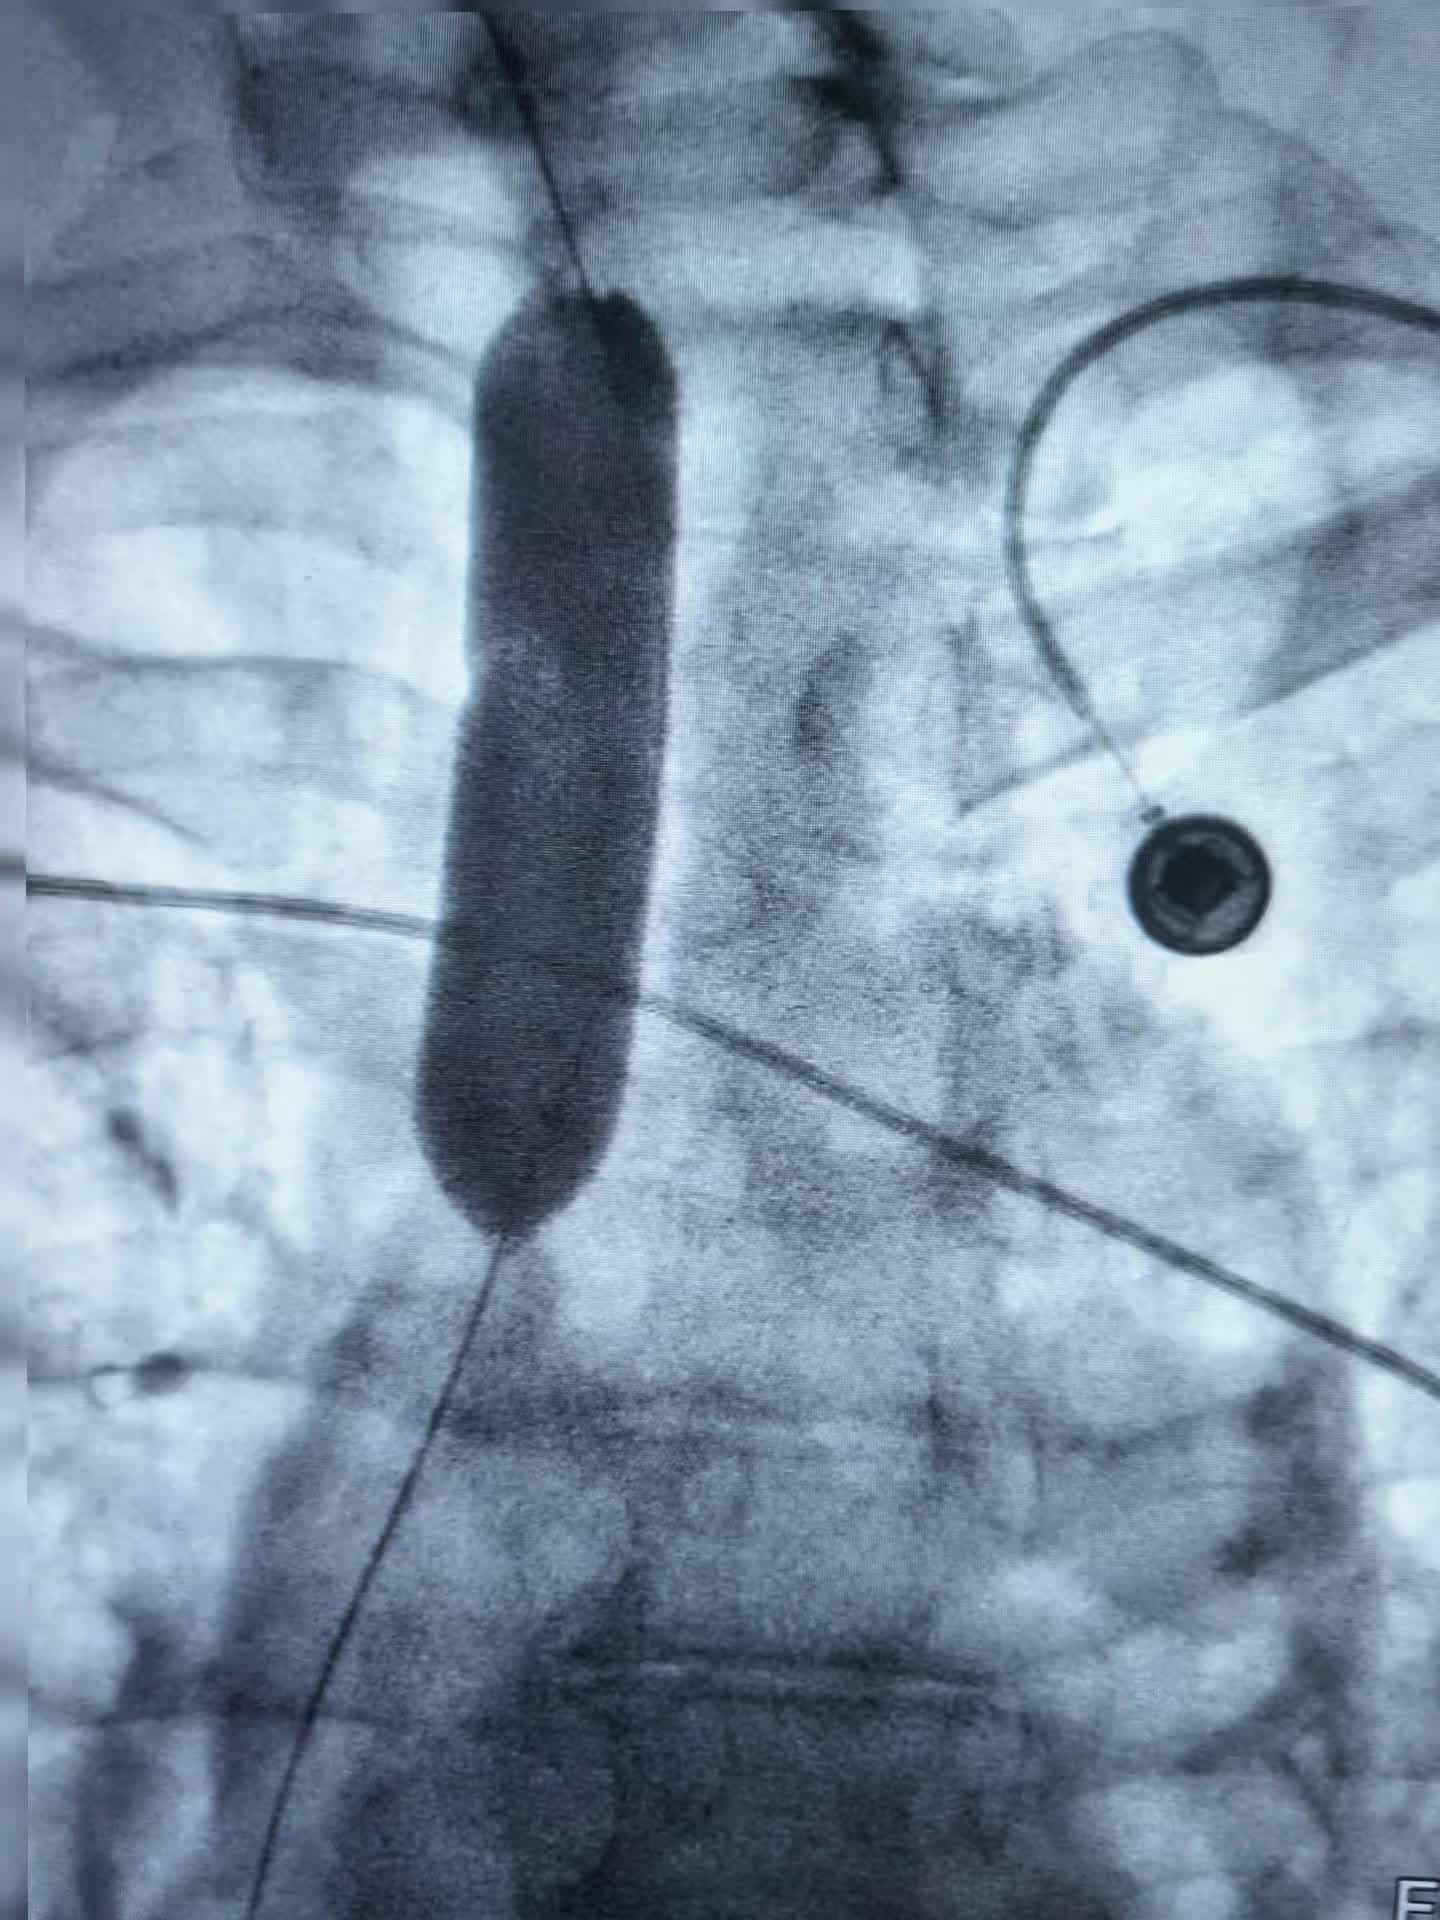

上午第一台78岁老年男性贲门癌患者,突发食管梗阻不能进食水,行球囊扩张,食管支架置入术,术即可恢复饮食。 第二台:食管癌术后3年再次进食哽咽,食管吻合口狭窄伴肠管膈肌处狭窄。单纯行球囊扩张术,术后即可恢复正常饮食。